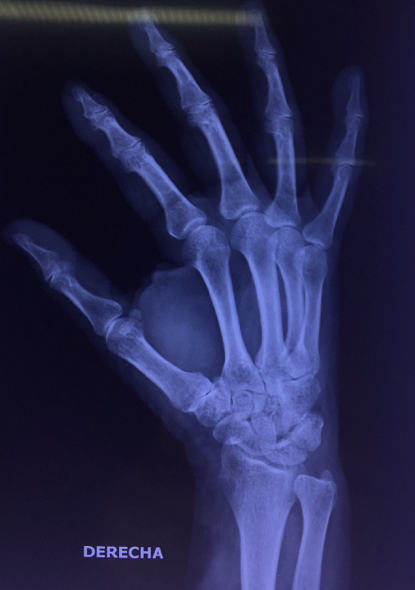

Comparto las fotos de la paciente, tanto las que fueron tomadas en aquella época como las actuales, en que podemos ver la movilidad que ha alcanzado y como esta le ha permitido mantenerse en sus actividades habituales sin dolor.